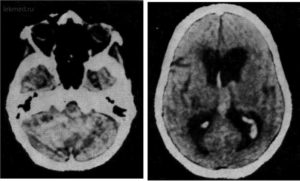

Острые нарушения кровообращения в мозжечке составляют инфаркты (некроз) либо кровоизлияния, которые имеют схожие механизмы развития с другими формами внутримозговых инсультов, поэтому факторы риска и основные причины будут совпадать. Патология встречается у людей среднего и пожилого возраста, чаще обнаруживается среди мужчин.

На долю инфаркта мозжечка приходится около 1,5% всех внутримозговых некрозов, в то время как кровоизлияния составляют десятую часть всех гематом. Среди инсультов именно мозжечковой локализации примерно ¾ приходится на инфаркты. Смертность высока и в иных случаях превышает 30%.